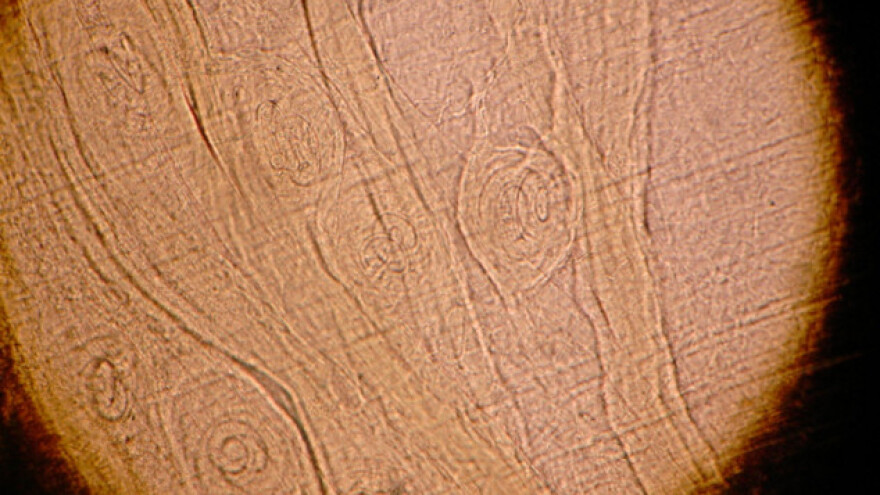

"Neophodno je izvršiti pregled svih kategorija svinja, od prasadi do krmača tovljenika na trihinelozu. Mesta za odlazak larvi trihinele su mišićni deo korena dijafragme, međurebarni mišići, mišići korena jezika i grkljan. Ono što se najčešće donosi na pregled, to je koren dijafragme preko koga se vrši pregled donetog uzorka. Pregled se vrši metodom kompresije i metodom digestije, na uzorku se prepoznaju larve, čime se meso proglašava neupotrebljivim", kaže doktorka Filimonović.